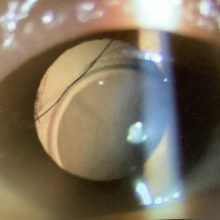

進行白内障の問題点

2024.02.24

今日は午前のみの外来で、手術の申し込みは、白内障2人、ICL1人、霰粒腫1人(49歳女性)でした。 今日、白内障の術前検査で受診された50代の女性の方は、水晶体が真っ白に濁った“成...